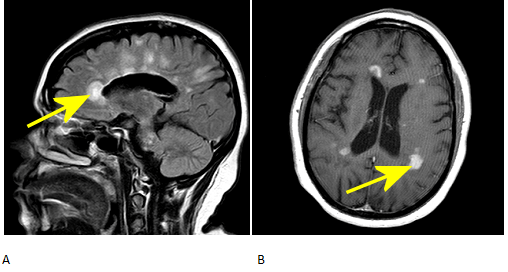

Demielinizarea lasă în urmă plăci în creier. Acestea sunt adesea vizibile pe scanările creierului. Degetul lui Dawson se dezvoltă în jurul unei benzi de fibre nervoase care leagă emisferele stângă și dreaptă ale creierului. Plăcile se formează în unghi drept în jurul venelor din ventriculii creierului.

Degetele lui Dawson sunt doar un semn de deteriorare care poate indica SM. Dacă o scanare a creierului arată degetele lui Dawson, dar o persoană nu are alte simptome sau dacă a avut un singur atac de SM, medicul său ar putea continua să le monitorizeze.